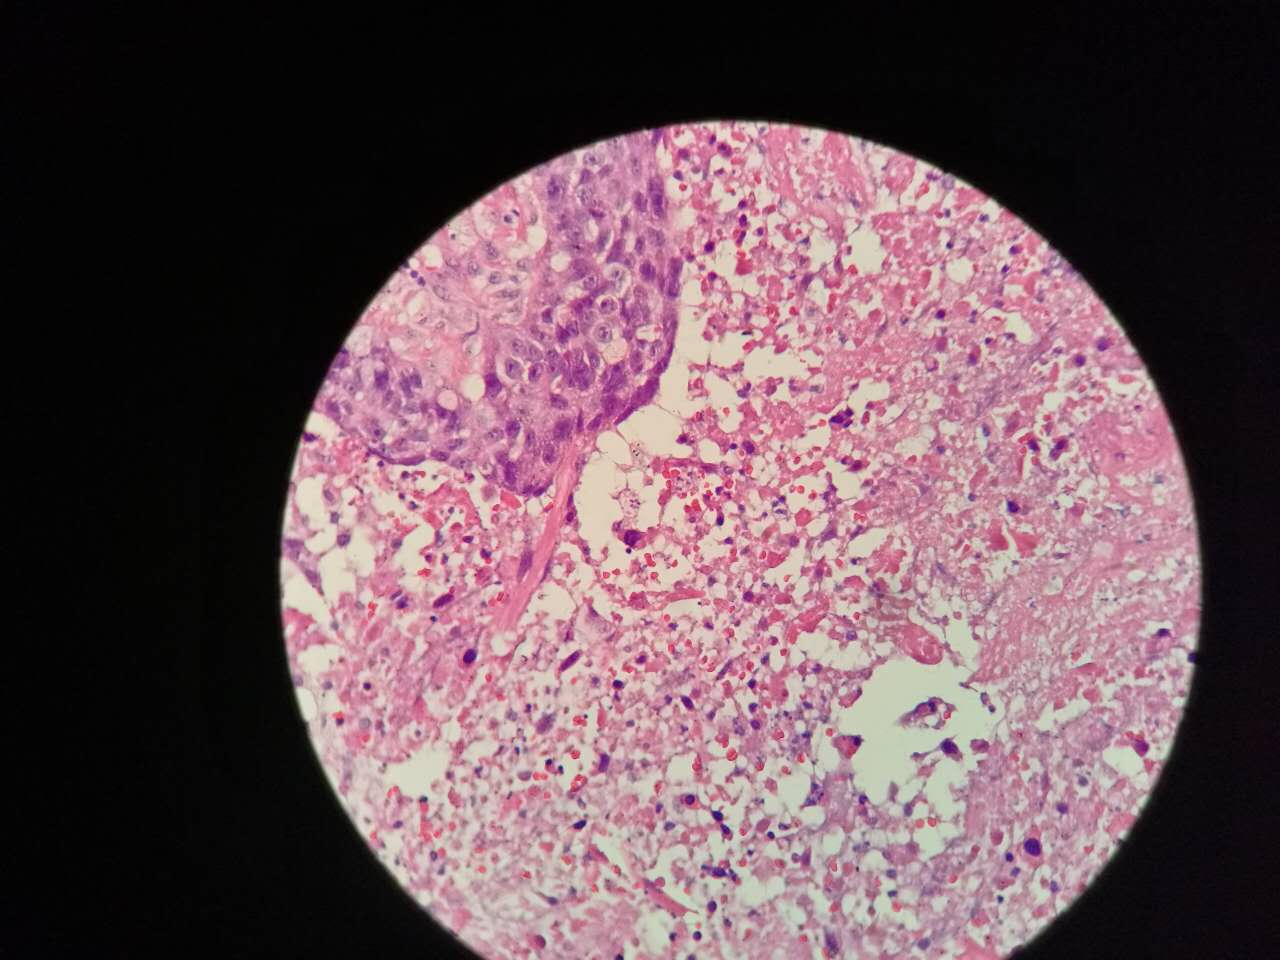

左手边有一点鳞癌,右手边有正常肺泡组织,中间有坏死物,这是为什么呢?

坏死物质渗出。

并且可以有吞噬,坏死物里常有血液成分

剖面多呈黄色

肿瘤周围不应是缺血,坏死一般在巢团内